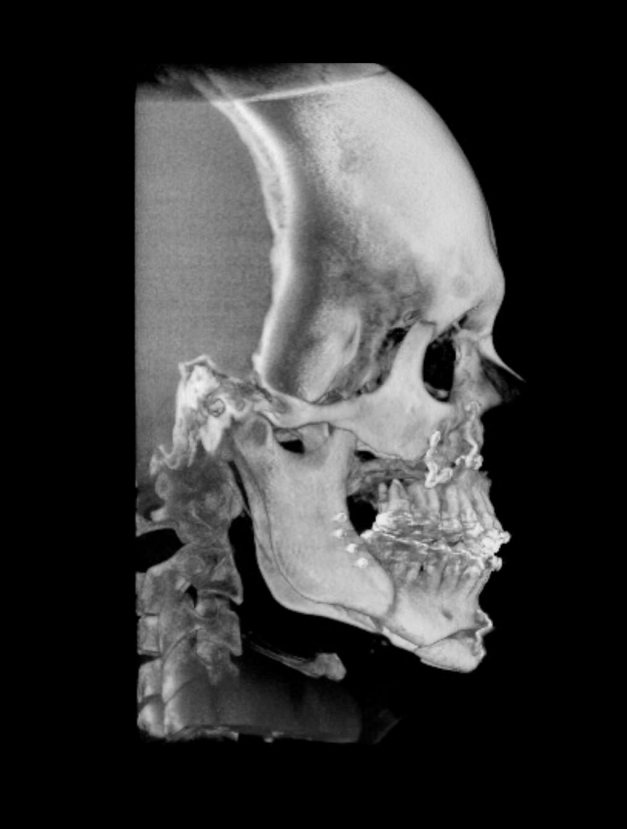

TC de face (do Hióide à Glabela), reconstrução 3D do tecido ósseo, radiografia panorâmica, telerradiografia lateral com traçado, cortes transversais e axial de maxila e mandíbula e arquivo DICOM- entregue em pasta de Pvc.

TC de face (do Hióide à Glabela), reconstrução 3D do tecido ósseo, radiografia panorâmica, telerradiografia lateral e frontal com traçado, cortes transversais e axial de maxila/mandíbula e arquivo DICOM – entregue em pasta de Pvc.

TC de face (do Hióide à Glabela), reconstruções 3D do tecido mole/ósseo/vias aéreas, radiografia panorâmica, telerradiografia lateral e frontal com traçado, cortes transversais e axial de maxila/mandíbula, ATM e arquivo DICOM – entregue em pasta e caixa de Pvc.